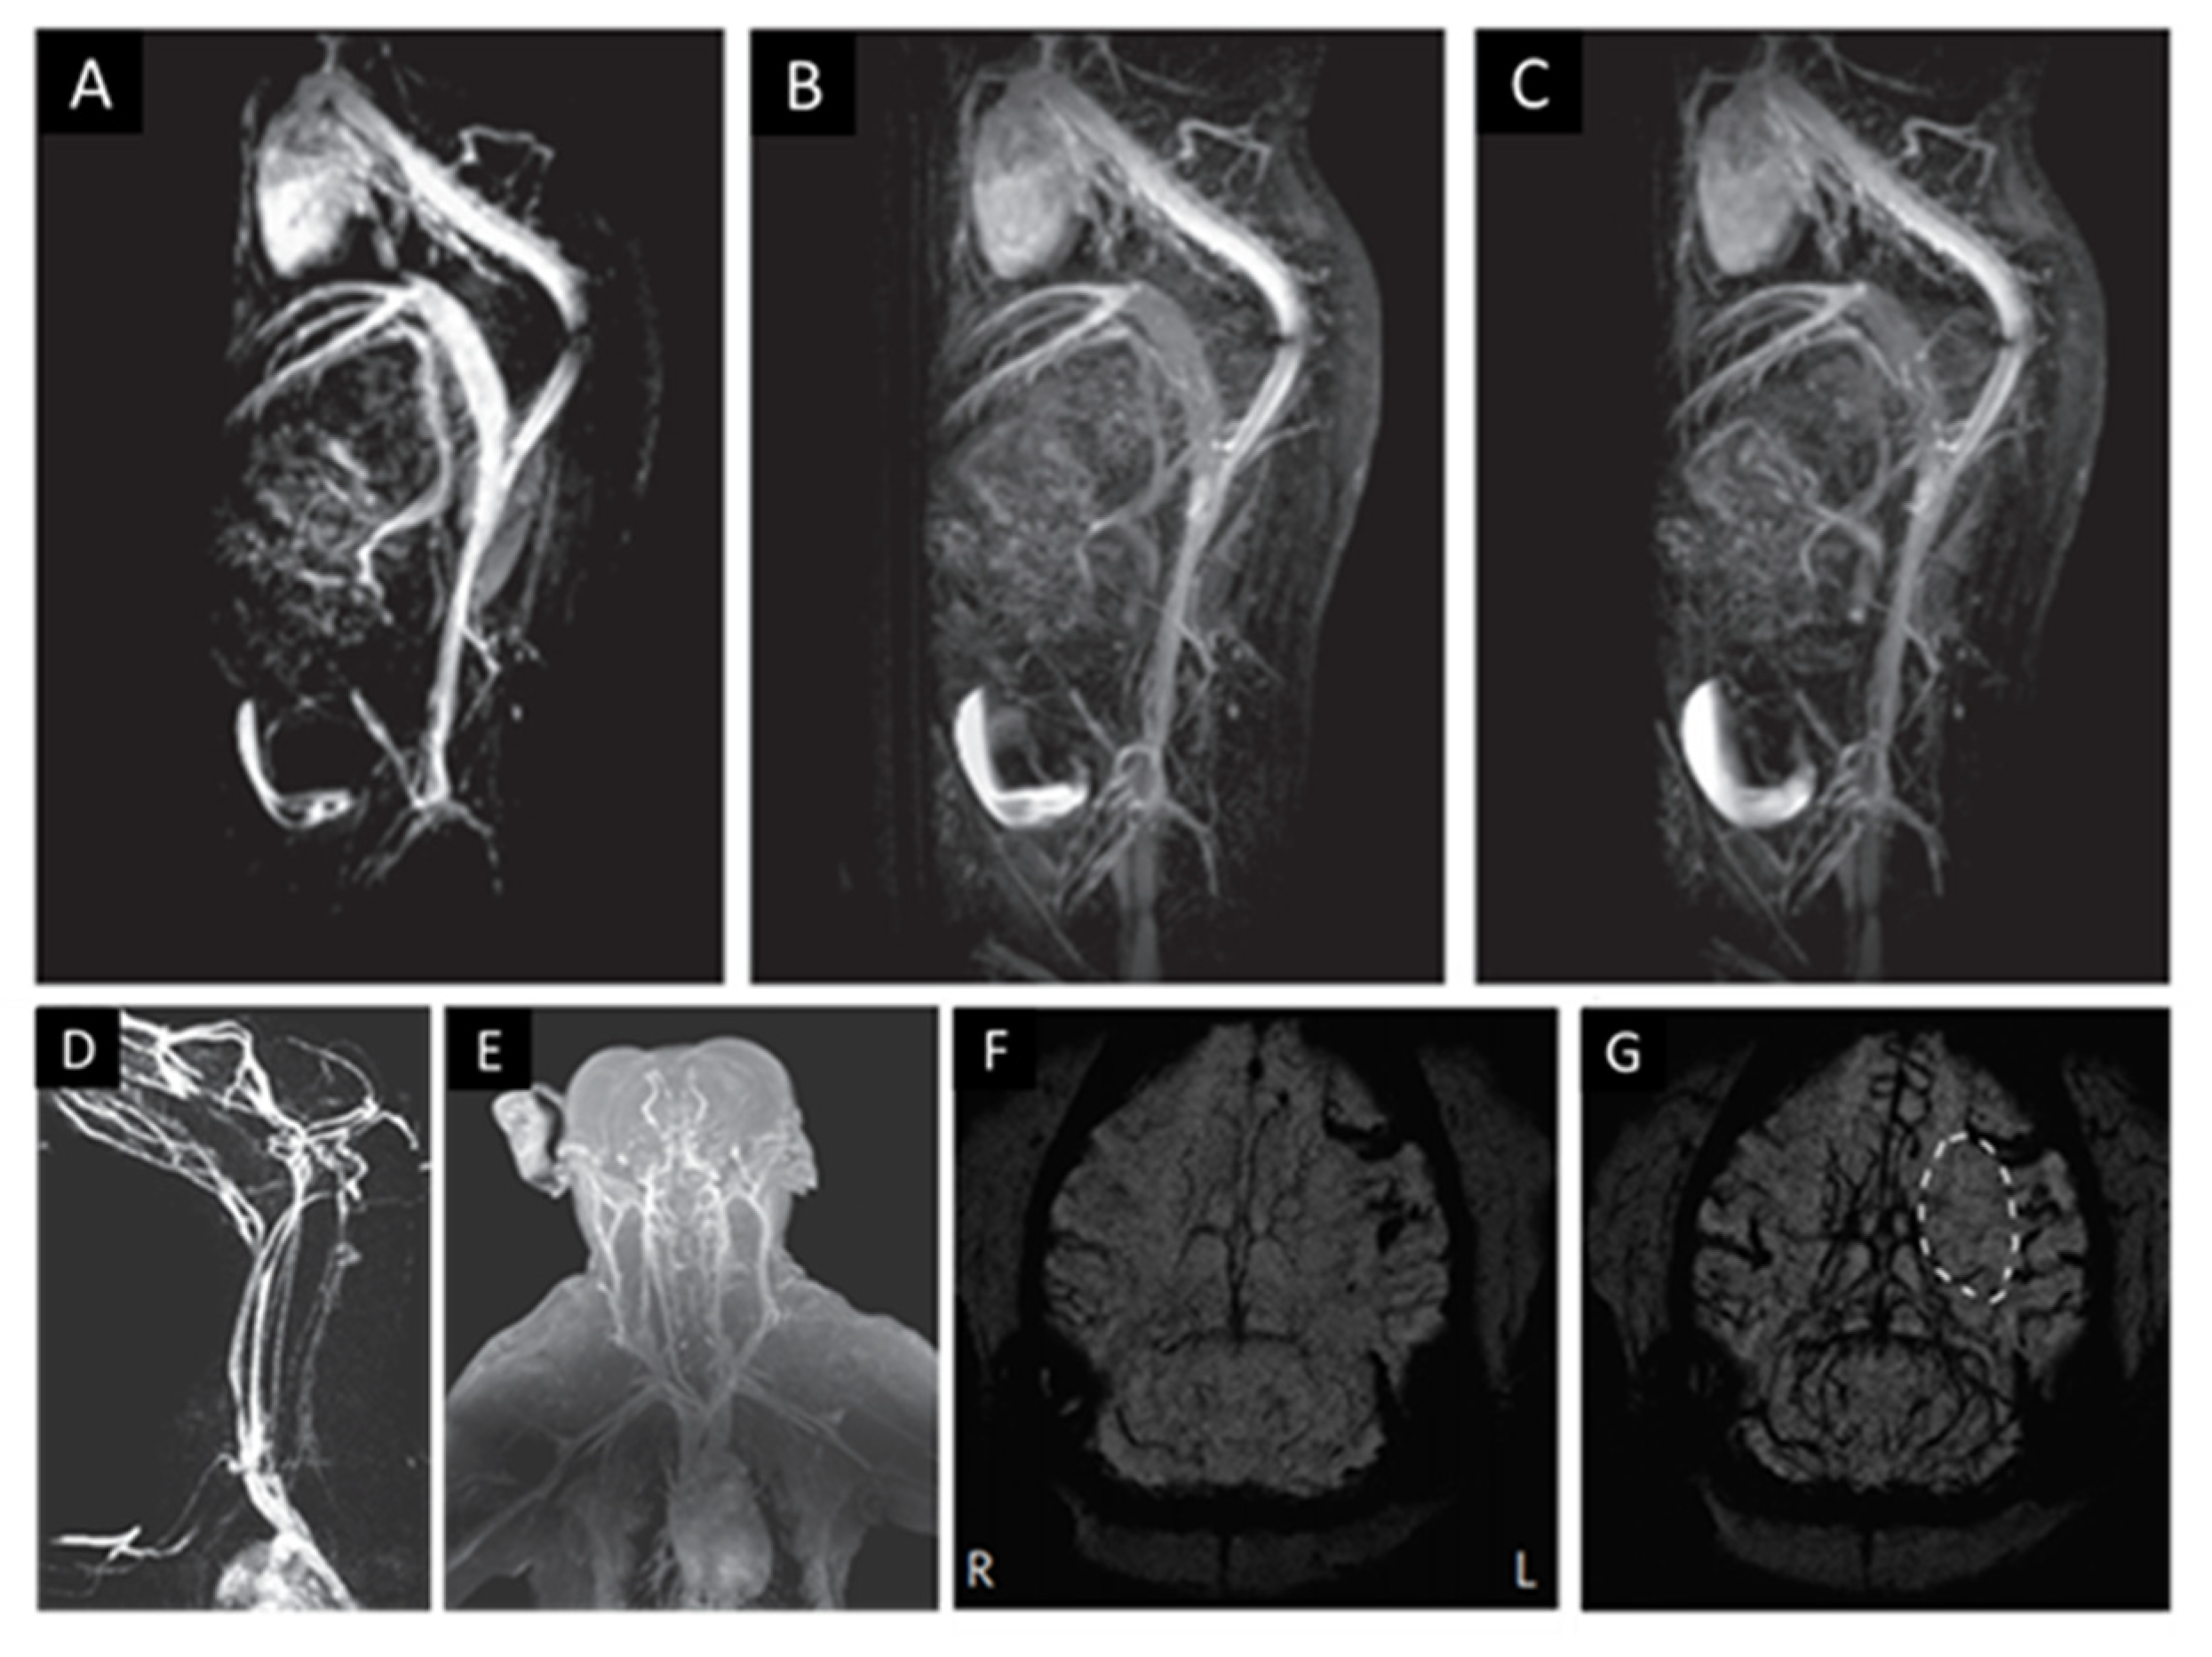

- Kang, M.; Jin, S.; Lee, D.; Cho, H. MRI Visualization of Whole Brain Macro- and Microvascular Remodeling in a Rat Model of Ischemic Stroke: A Pilot Study. Sci. Rep. 2020, 10, 4989. [Google Scholar] [CrossRef] [Green Version]

- Barajas, R.F.; Hamilton, B.E.; Schwartz, D.; McConnell, H.; Pettersson, D.R.; Horvath, A.; Szidonya, L.; Varallyay, C.G.; Firkins, J.; Jaboin, J.J.; et al. Combined iron oxide nanoparticle ferumoxytol and gadolinium contrast enhanced MRI define glioblastoma pseudoprogression. Neuro-Oncology 2019, 21, 517–526. [Google Scholar] [CrossRef]